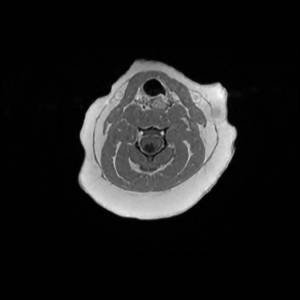

Main Gallery

Playing with a photo gallery function. It is possible to have multiple galleries, each within a namespace.